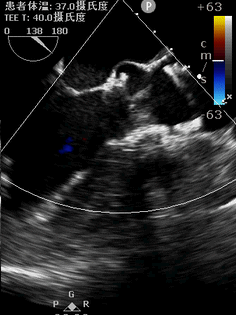

患者入院后完善相关检查,并给予药物支持治疗。术前检查我们发现患者先天性主动脉瓣二叶式畸形 主动脉瓣重度狭窄伴轻中度关闭不全,左室明显增大(LV 60),心功能测值降低(EF% 48%)(图1,2),同时合并升主动脉瘤样扩张(AAO 45)(图3,4)。心脏大血管外科胡佳教授对患者进行了全面的评估,反复与患者沟通手术相关风险和花费后决定为患者实施胸腔镜下肋间小切口免缝合主动脉瓣置换+升主动脉成形术。该方法既可以微创不损伤胸骨,免缝合主动脉瓣术中无需缝合打结,大大缩短体外循环和心脏阻断时间,降低手术风险,又可以在一定程度上降低患者总体费用。完善术前相关准备后手术如期进行。